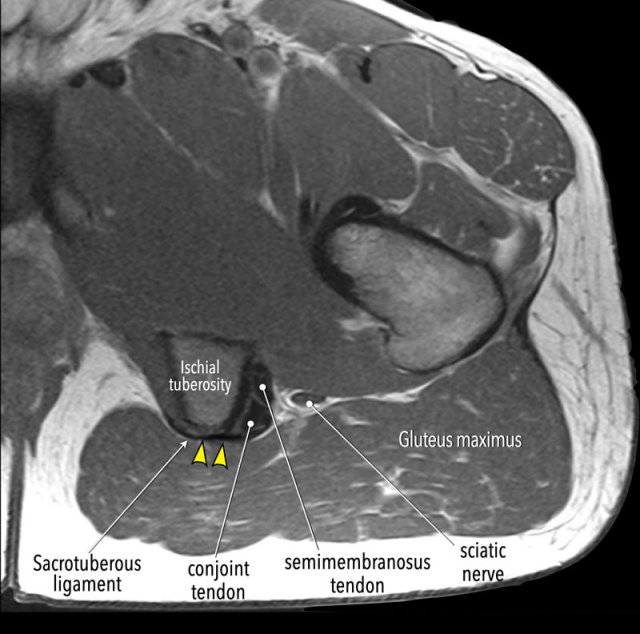

On this axial MR-image note the aponeurotic connection between the sacrotuberous ligament and the superficial part of the conjoint tendon.

In some cases, the tendons may be avulsed from the ischial tuberosity while this connection remains intact. In these cases no retraction will be present and surgery is usually not necessary.

It is best to determine which tendon is torn on axial images.

The ischial tuberosity can be regarded as an icecream cone with the tendon of the semimembranosus (anterolateral ) and the conjoint tendon (posteromedial ) as two scoops with the flavor StracciatelLa CaraMel.

The image shows an avulsion of the semimembranosus tendon.

① tendon of the semimembranosus

② conjoint tendon

Remember the flavours:

Stracciatella - Semimembranosus lateral

Caramel - Conjoint medial